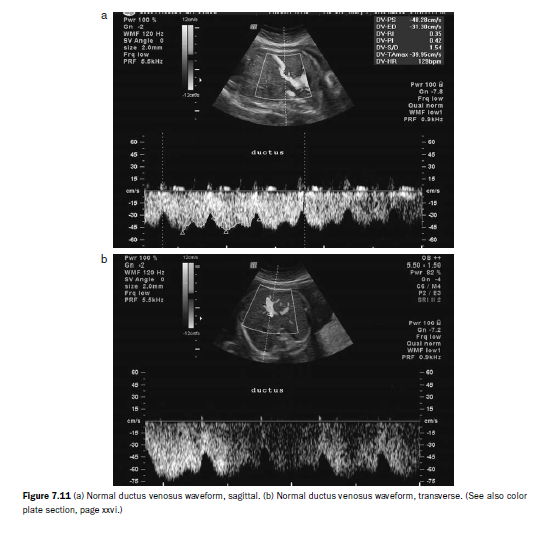

Doppler interrogation of the ductus venosus can be particularly challenging in the assessment of patients with TTTS. Care must be taken not to confuse the waveform of the ductus venosus with that of the hepatic veins or the inferior vena cava (Figure 7.11a–e: DV, hepatic vein, IVC).

Similarly, the WMF should be set at 100 MHz. For the purposes of the staging system, flow in the ductus venosus must be reversed during the atrial contraction waveform to be called critically abnormal, and not merely absent (see Figure 7.10).